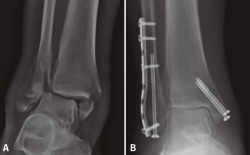

A nivel de partes blandas, las placas bloqueadas con un diseño de bajo perfil y precontorneadas favorecen la contención de fragmentos pequeños y la menor irritación de la piel. Sin embargo, debe tenerse en cuenta el grosor de la placa y si contamos con suficiente piel para la cobertura de esta por posibles complicaciones(29,31). Existe la posibilidad de la colocación percutánea de la placa para una menor agresión de las partes blandas (Figura 3).

Figura 3. A: placa de tercio de caña bloqueada (con tornillos no bloqueados en la zona proximal); B: implante mediante técnica percutánea; C: incisiones finales.